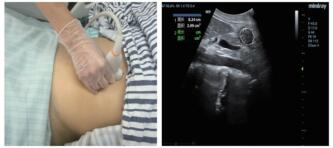

⑵超声测定截面积:由一位接受过急危重症超声规范培训的医师完成。使用M9便携式彩色多普勒超声诊断仪(深圳迈瑞公司),选择低频曲阵探头、频率2~5 MHz、标准腹部模式,患者分别于半坐位、平卧位与右侧卧位三种体位,探头置于上腹部矢状位或旁矢状位扫描,以腹主动脉、肠系膜上动静脉为定位标志获取胃窦图像,应用自由追踪描记技术描记胃窦截面的轮廓范围,取三次测量数据的平均值后计算胃窦截面积(见图 2)。

|

| 图 2 床旁超声检测胃窦截面积的方法(左:探头位置;右:胃窦截面轮廓描记) Fig 2 The cross-sectional area of gastric antrum measured by bedside ultrasound (Left, probe position; Right, outline tracing of gastric antrum cross-section) |